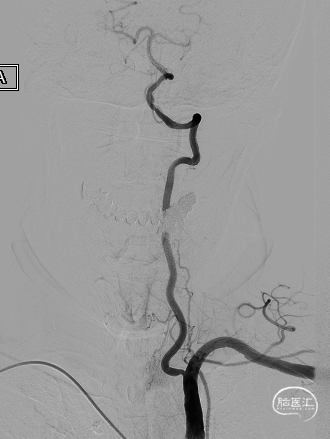

扩张完毕后多角度造影显示狭窄较前明显改善(箭头处)。

撤出保护伞观察10分钟复查造影,无弹性回缩,狭窄明显好转,血流明显改善(箭头处),结束手术。